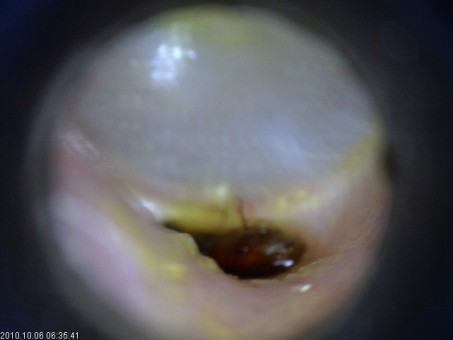

- Tratamentul otitelor externe si medii prin aspirarea secretiilor si tratament local